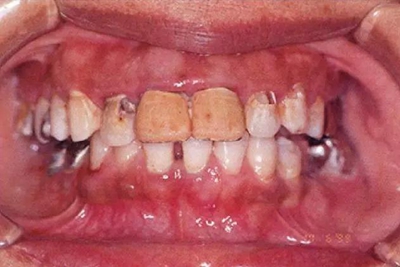

患牙齦炎的牙周組織的臨床圖像

22歲男性牙齦炎的臨床圖像

22歲男性,抽煙(1天約15根,煙齡5年)。刷牙狀態(tài)不佳。抽煙者特有的纖維性牙齦,未見發(fā)紅、腫脹。探針觸診,所有部位均出血。X線牙片未見骨吸收,診斷為牙齦炎。

14歲男性牙齦炎的臨床圖像

14歲男性。刷牙狀態(tài)不佳。整顎浮腫性發(fā)紅、腫脹且刺激出血。牙頸部有早期齲(白斑)。